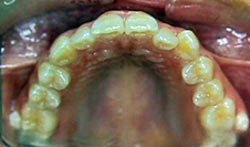

FIGURA 4 Foto Intrabucal Oclusal superior

Las fotos finales de este caso se observan a continuación (Figuras 15, 16, 17, 18, 19)

FIGURA 18 Foto Intrabucal Oclusal superior